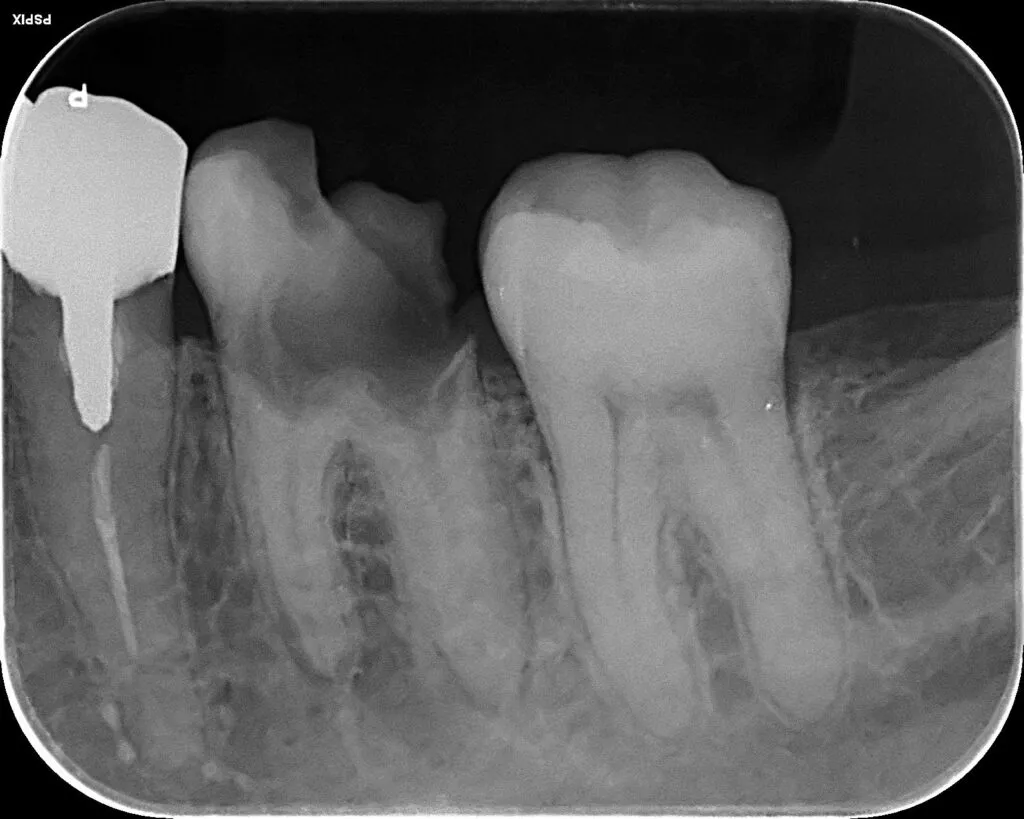

インプラント治療症例①

インプラント治療症例②

インプラント治療症例③

インプラント治療症例④

インプラント治療症例⑤

インプラント治療症例⑥

歯周病などで骨が少なくなった患者さんに対して行う、骨を再生させる処置(ソケットプリザベーション)